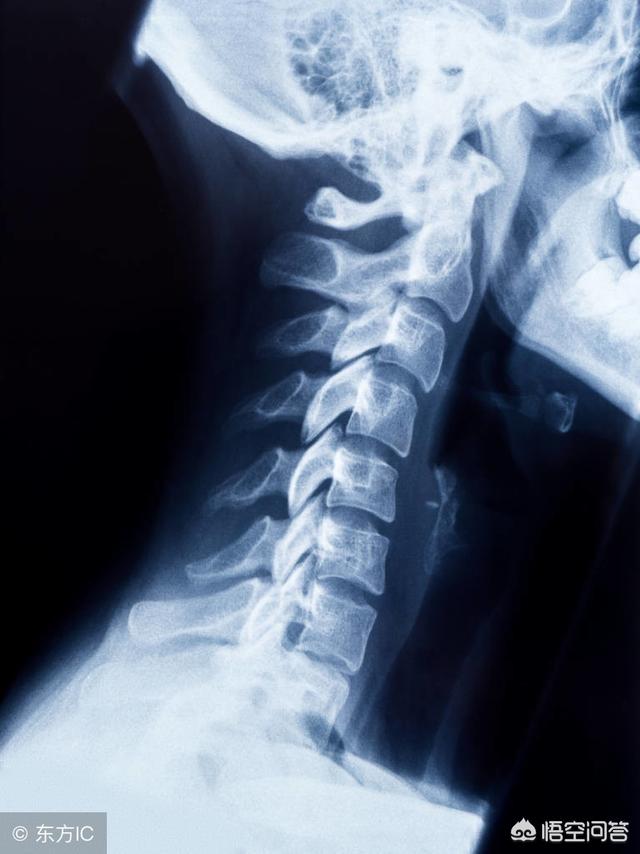

颈椎反弓能恢复吗(如何治疗颈椎生理曲度反弓)

17岁很年轻,不过对于现在高中生来讲,生理曲度变直或者反弓的真不在少数,矫正不麻烦,不过矫正之前要有一个大的前提,排除病理因素的影响。

举例,颈椎病造成的生理曲度反弓,也要在颈椎症状消失之后,再考虑矫正的问题,不然生理曲度反弓是一种代偿性的保护的话,盲目矫正会导致症状加重,症状的存在也会仍然导致反弓再次形成。

话不多说,讲一下怎么矫正生理曲度反弓,主要包含三个方面,第一,放松颈部肌肉;第二,归位紊乱的小关节;第三,枕毛巾或者浴巾。